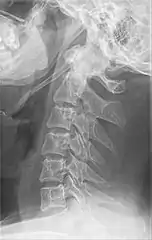

| Anteroposterior and lateral radiographs of cervical spine showing ossification of the stylohyoid ligament on both sides | |

Radiograph, lateral view showing elongated stylohyoid process and stylohyoid ligament ossification